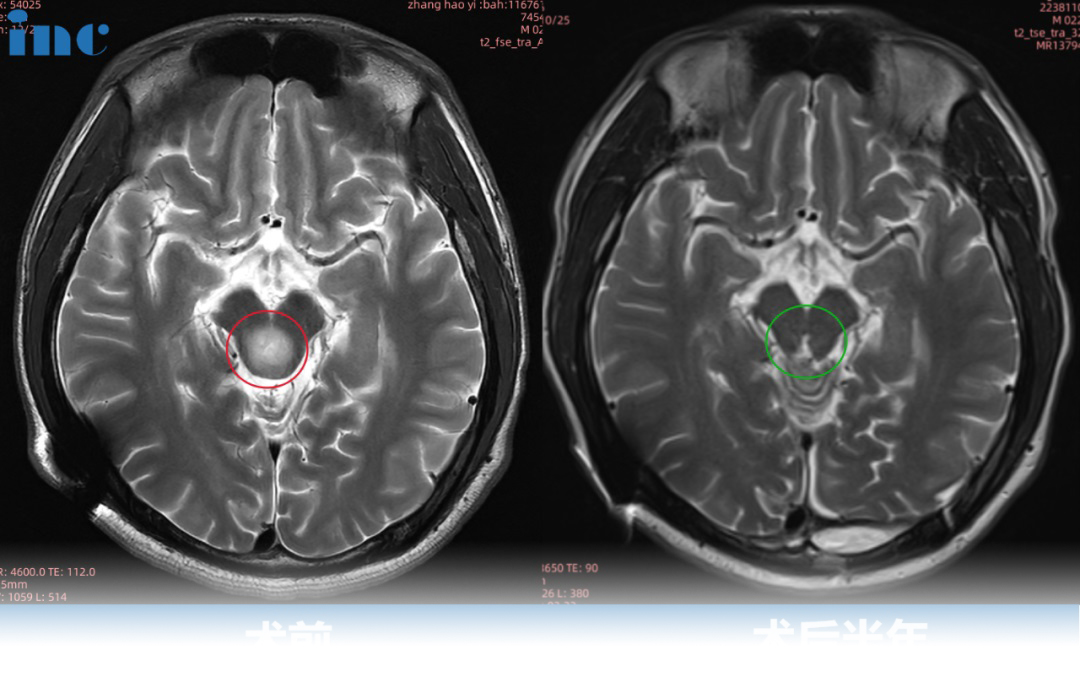

2021年2月张远不幸MRI检查出中脑顶盖占位性病变,疑似胶质瘤,较大直径约8mm,2022年8月张远病情再次加重,复查磁共振提示肿瘤增大,此时肿瘤较大直径12mm,2022年10月复查核磁提示肿瘤增大,自行测量肿瘤大小约18mm,两月内竟激增6mm!肿瘤越来越大,然而四处寻医的结果却是脑干位置风险太大,无法手术。但是家人并没有放弃,然后在2022年巴教授示范手术期间,巴教授顺利为张远近全切肿瘤。在巴教授顺利为张远进行近全切手术后,术后半年随访中,张远恢复良好,行动自如。巴教授查看了他的复查影像后回复道:

2022年8月张远病情再次加重,眼球活动受限,眼球向下运动困难,后脑勺偶然还会感到麻木或疼痛。复查磁共振提示肿瘤增大,此时肿瘤较大直径12mm,一年半内生长4mm。

然而,这个肿瘤不曾停止生长,2022年10月复查核磁提示肿瘤增大,自行测量肿瘤大小约18mm,两月内竟激增6mm!

远程咨询巴教授报告回复:这个中脑肿瘤是有明确的手术切除指征,在近期一段时间内肿瘤尺寸不断增大。长时间等待只会给肿瘤更多的生长机会,并对脑干产生危险,从而(加重)影响患者的临床状态。我附上了2022年08月05日(前四片)和2022年10月11日(然后三片)磁共振截图。就在这两个月内,肿瘤的进展明显。